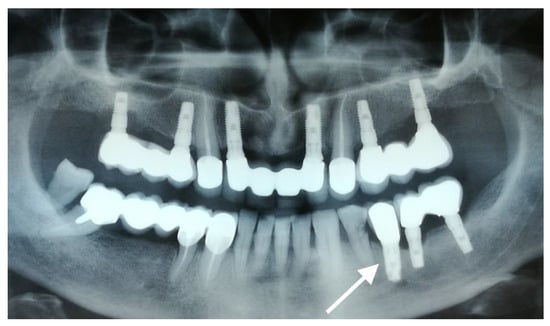

The second implant (Sample 2) was recovered from a 55-year-old male patient and was inserted in position 3.4 (Figure 3, arrow). The rehabilitation included a PFM crown. The patient presented with pain and mobility of dental implants in quadrant 3. Following the clinical examination, poor oral hygiene was detected by the presence of calculus and soft plaque deposits. The implants in quadrant 3 showed gingival retraction and exposure of the first grooves of the cervical segment to the oral cavity. The patient interview revealed he was a heavy smoker (of around 30 cigarettes per day) and suffered from arterial hypertension treated with prescribed medication.

Figure 3. OPG radiography revealing peri-implantitis-affected areas. Quadrants 3 and 4 show bone loss extended to the apical segments of the implants, while quadrants 1 and 2 show a goblet-shaped bone loss. The studied implant is marked with an arrow.